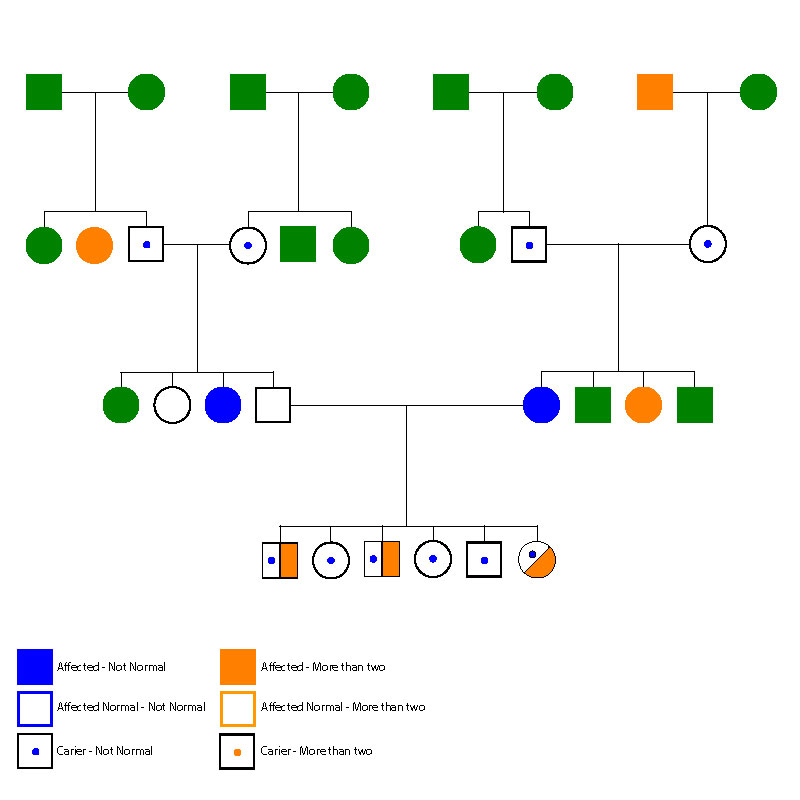

The best pedigree for this purpose is called the Symbols Pedigree. It relies on vertical and horizontal information about the ancestors. It is easy to use the two symbols. Squares are used to represent the males and circles to represent the females. This pedigree places emphasis on the breadth of a pedigree, meaning the littermates of each ancestor. It relies on the logic that a pedigree can be understood by learning about the traits and characteristics observed among the littermates of each ancestor. This approach provides horizontal and vertical information and is effective for making improvements in the core elements of health, performance, temperament and other specific traits of interest. The inclusion of littermates distinguishes this pedigree from all others.

Figure 2 Symbols Pedigree

Information is coded using designated colors that represent specific traits or diseases. Because breeders are interested in many traits and diseases, several colors are used to code their pedigrees. The repetition of a color signals that a genetic trend or pattern may be present. In this example (Figure 2) green indicates that no information has been collected. Blue and orange are used to code specific traits. A dot of any color indicates a carrier for a trait. In Figure 2, the coding shows 10 carriers (dot) among 31 ancestors. In a real case this would be a concern to a breeder.